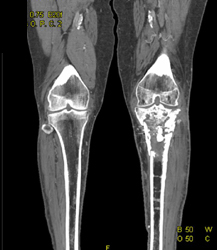

Diagnosis

High Grade Celiac Artery Stenosis